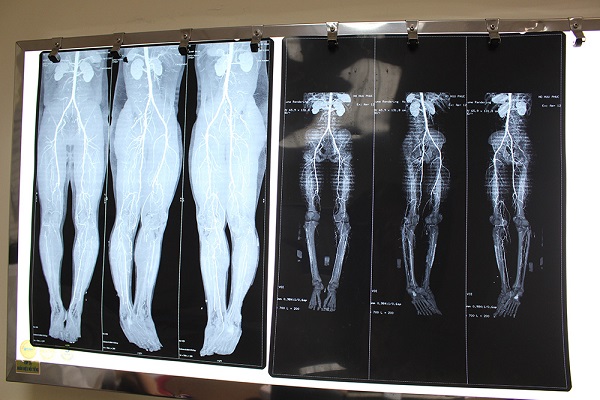

Kỹ thuật chụp mạch máu kỹ thuật số xóa nền DSA đã phát hiện chàng trai bị tắc mạch máu chân phải, kịp thời giữ lại chi trước khi hoại tử. Ảnh: Phú Mỹ

Tại đây, qua kiểm tra và chụp CT mạch máu chân phải, bác sĩ phát hiện bệnh nhân bị tắc hoàn toàn nhiều động mạch. Sau khi hội chẩn, bác sĩ quyết định dùng phương pháp can thiệp nội mạch với kỹ thuật chụp mạch máu kỹ thuật số xóa nền DSA nhằm xác định chính xác các thương tổn, bệnh lý mạch máu trước khi chỉ định can thiệp mạch. Kết quả chụp DSA cho thấy bệnh nhân đã bị tắc hoàn toàn các động mạch đùi nông, động mạch khoeo, động mạch chày trước và động mạch chày sau.

Các bác sĩ đã quyết định dùng phương pháp nong động mạch bằng bóng. Sau can thiệp, các động mạch bị tắc đã được tái thông hoàn toàn, các nhánh bên và tuần hoàn bàng hệ vẫn được bảo vệ đảm bảo tưới máu chi dưới tối ưu sau can thiệp.